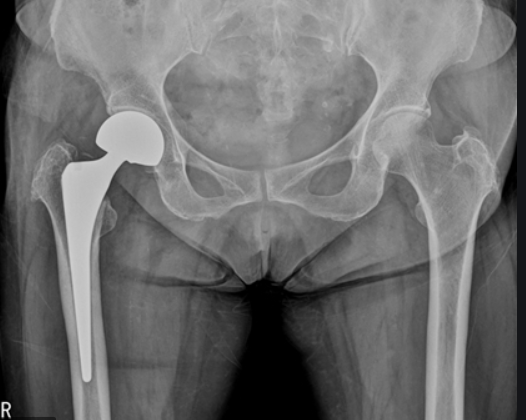

고관절 수술방법

고관절 수술방법으로는 보통 3가지 방법으로 나뉩니다. 첫번째로는 대퇴골두에만 구멍을 뚫어 혈관이 생설될 수 있는 통로를 만들어 자기 관절을 살리는 감압술을 하는 방법이 있습니다.

두번쨰로는 대퇴골두에만 인공뼈를 삽입하여 치환시키는 방법과 세번째로는 관절 부분 전체를 인공관절로 바꿔주는 방법이 있습니다. 이 경우에는 심하게 괴사가 된 경우에 사용하는 방법으로 합병증이 적고 기능개선이 우수하다고 알려져 있습니다.